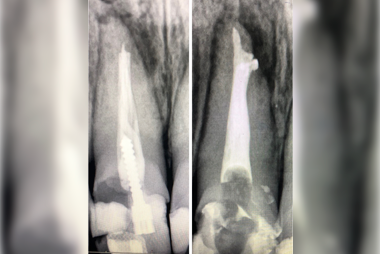

Kanal tedavisi, dişlerde oluşan çatlaklar ve kırıklar, dişte meydana gelen derin çürükler, dişte bulunan sinirler ve damarların canlılığını yitirmesi sonucu dişin kanallarında bulunan enfekte dokunun temizlenmesi, dezenfekte edilmesi ve kanal dolgu maddeleri ile doldurulmasına kanal tedavisi denir.